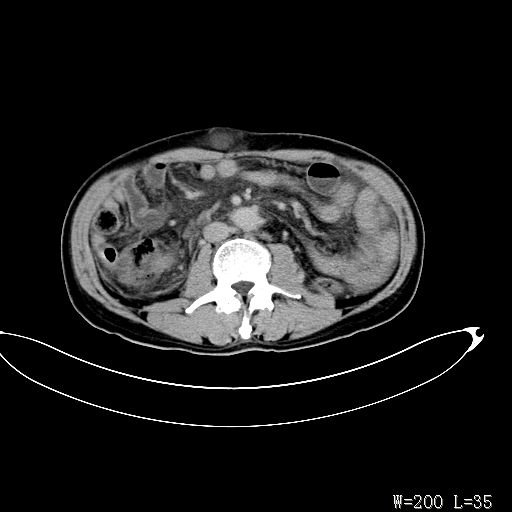

标题: CT27080:腹壁肿物?

男,52岁,门脉高压断流术后1年,发现腹部肿物2月。

1)前腹壁中线区(脐上方)囊性占位性病变,考虑淋巴囊肿。2)腹水。